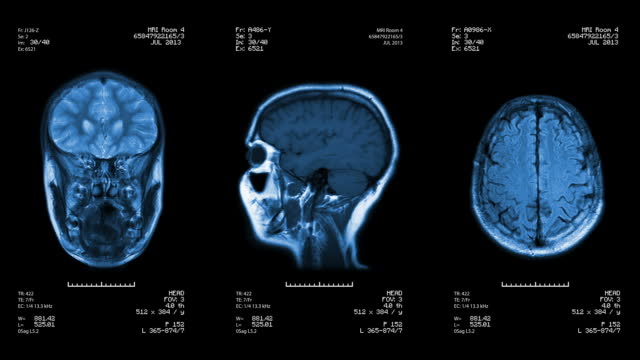

뇌경색 초기증상 후유증

급성 뇌경색을 겪은 환자들은 후유증을 남길 수 있습니다. 팔다리의 마비, 언어 장애, 식물상태 등이 후유증으로 나타날 수 있으며, 약 15% 정도의 환자가 1년 내에 사망할 수 있다고 알려져 있습니다. 그러나 효과적인 치료와 재활치료를 통해 많은 환자가 독립적인 삶을 되찾을 수 있으므로 희망을 갖고 치료에 임해야 합니다.

뇌경색 초기증상 예방법

급성 뇌경색을 예방하기 위해서는 건강한 생활 습관을 유지해야 합니다. 고혈압, 당뇨, 고지혈증과 같은 위험 인자를 관리하고, 금연 및 금주가 필요합니다. 또한, 체중 관리와 규칙적인 유산소 운동이 필요하며, 40대 이상의 성인은 정기적인 혈관 질환 검진을 고려해야 합니다. 최신 검진 프로그램을 활용하여 혈관 건강을 확인하고 조기 발견과 조치가 중요합니다.

급성 뇌경색은 심각한 질환으로서 조기 발견과 치료가 생명을 구하는데 결정적인 역할을 합니다. 따라서 뇌경색과 관련된 증상이나 위험 인자가 있을 경우 즉각적인 의료 조치를 통해 치료를 받는 것이 중요합니다. 또한, 건강한 생활 습관을 유지하여 뇌경색을 예방하는 노력이 필요합니다.